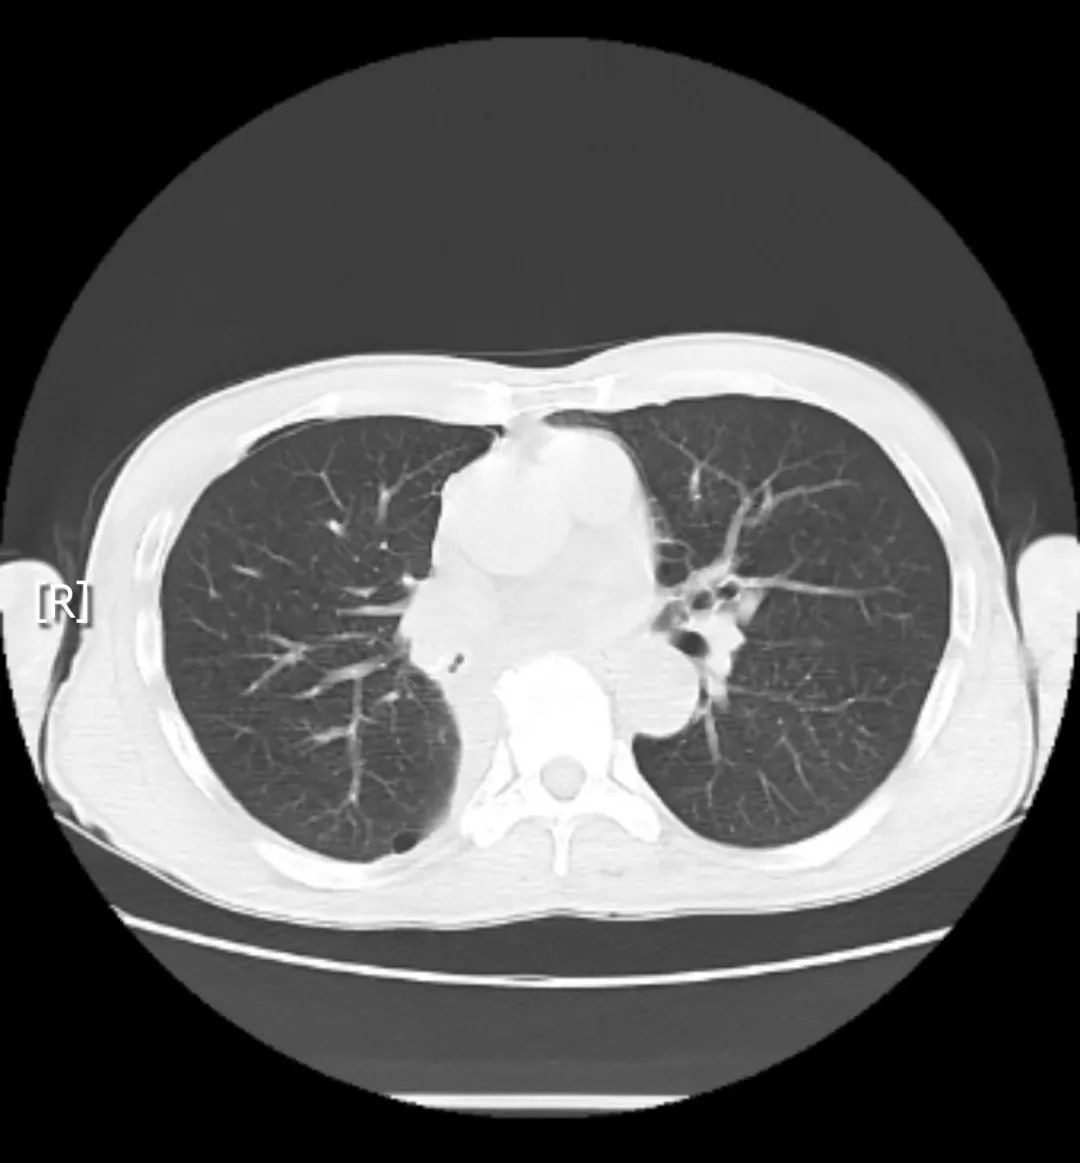

患者刘某某,男,59岁,因反复咳嗽、咳痰伴气促2月余,在当地治疗无效后于3月来我院就诊。经高分辨率CT检查提示右肺下叶占位性病变,右肺下叶背段支气管变窄,支气管镜检发现右下肺开口处肿物,病理确诊为肺鳞癌。面对肿瘤位于支气管开口的特殊解剖位置,采用传统的手术方式要保证切缘距离,可能会切除患者右中叶,术后肺功能恢复慢,生活质量欠佳。考虑到手术的特殊性,科室迅速启动MDT多学科会诊,经术前评估讨论,排除手术禁忌症,与患者及家属充分沟通后决定实施高难度胸腔镜下右下肺癌根治术联合支气管成形术。

在邵阳市中心医院刘晓飞教授指导下,胸外乳甲科付立波副主任医师、苏才杰副主任医师、聂雄英医师及麻醉护理团队共同协作,于术中切开右中间干支气管,中叶支气管开口无异常,右下叶支气管开口见肿瘤,肿瘤上缘剪断下叶支气管,修剪中间干支气管,支气管残端剪取一圈送快速冰冻病检,病检提示支气管残端未见癌细胞,遂对中叶支气管与中间干支气管进行成型。手术历时2小时顺利完成。 术后第2天,患者便可下床活动,复查肺部CT:显示右肺中叶及上叶复张良好,胸腔内无积液、积气。 患者恢复良好,术后康复出院,表示非常满意。

术前胸部CT